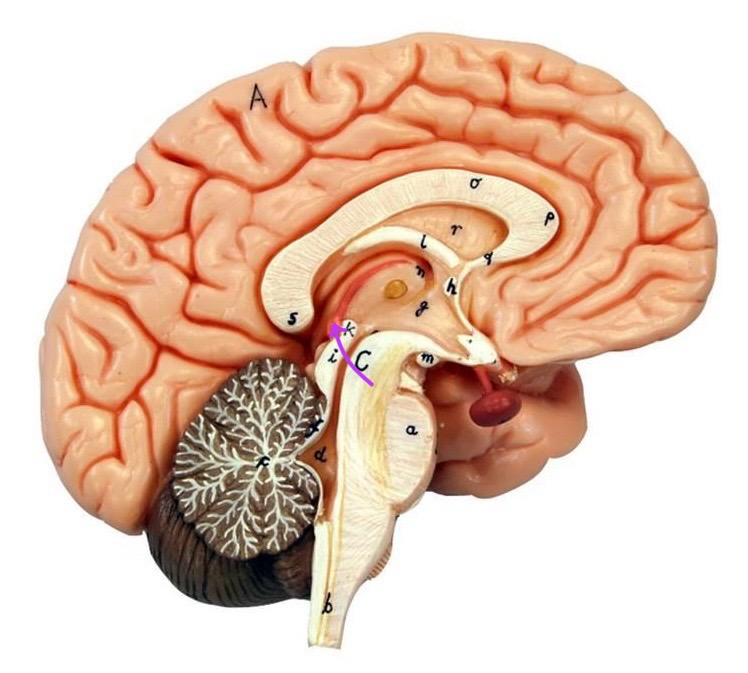

What is D?

lateral ventricle

Imagine thin membrane separating the 2 lateral ventricles

septum pellucidum

What is C?

3rd ventricle

What is B?

cerebral aqueduct

What is A?

4th ventricle

What is below A at the very end?

central canal (spinal cord)

What is C?

midbrain

tectum (corpora quadrigemina): superior colliculus

tectum (corpora quadrigemina): inferior colliculus

What is a?

pons

medulla oblongata

intermediate mass of thalamus

hypothalamus

What is the pink bulb?

pineal gland

corpus callosum

fornix

What is A?

cerebral cortex

cerebral tracts

cerebral hemispheres

longitudinal fissure

What are these ridges?

gyri

What are these shallow grooves?

sulci

Divides parietal from frontal lobe

central sulcus

precentral gyrus

postcentral gyrus